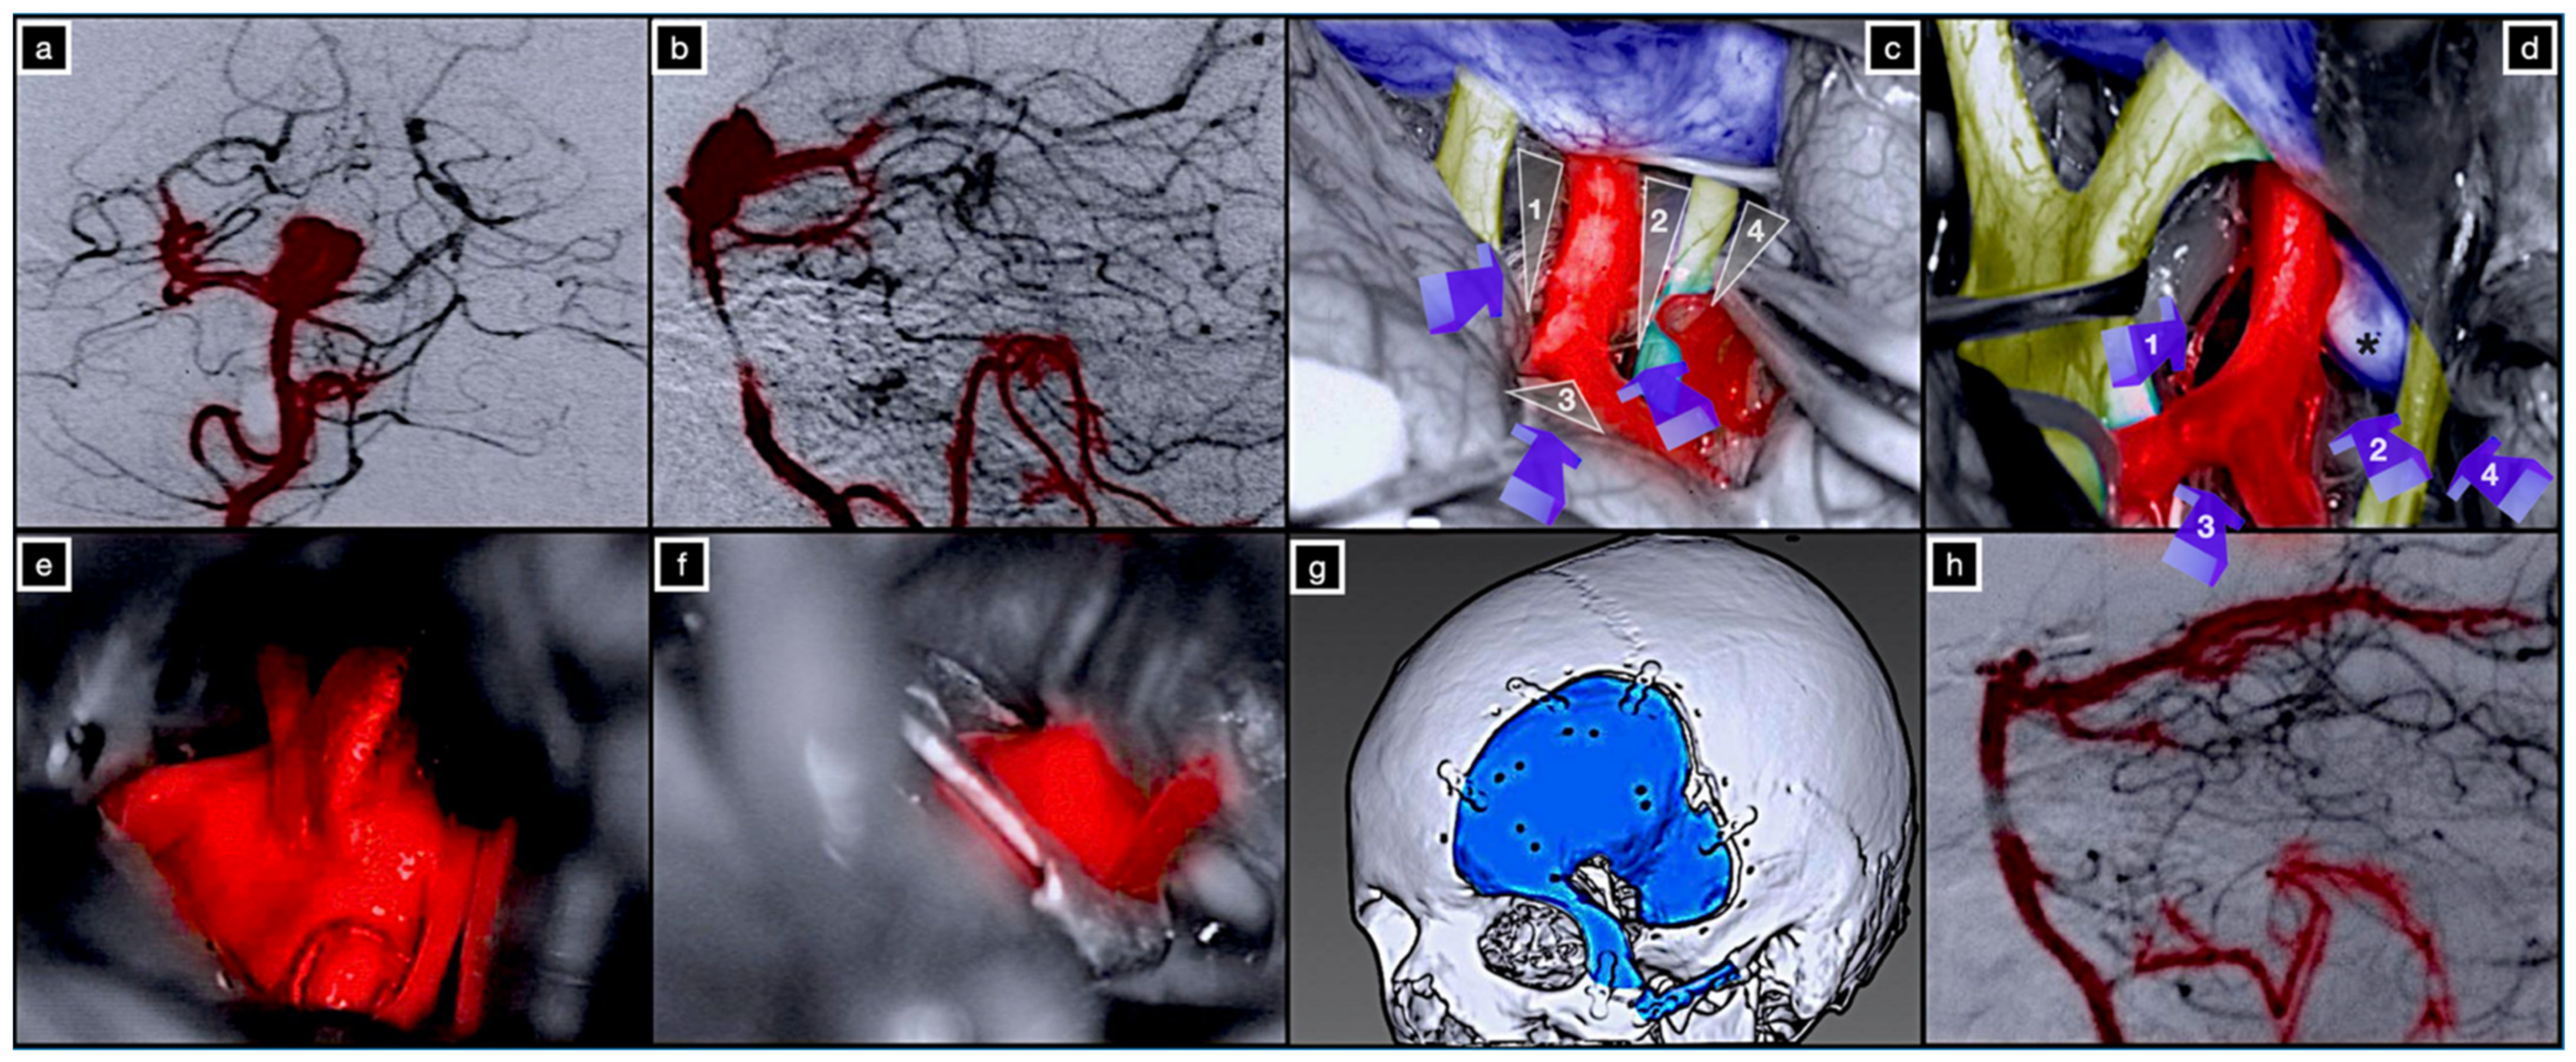

3.3.1. Case 1: Complex Basilar Tip Aneurysm